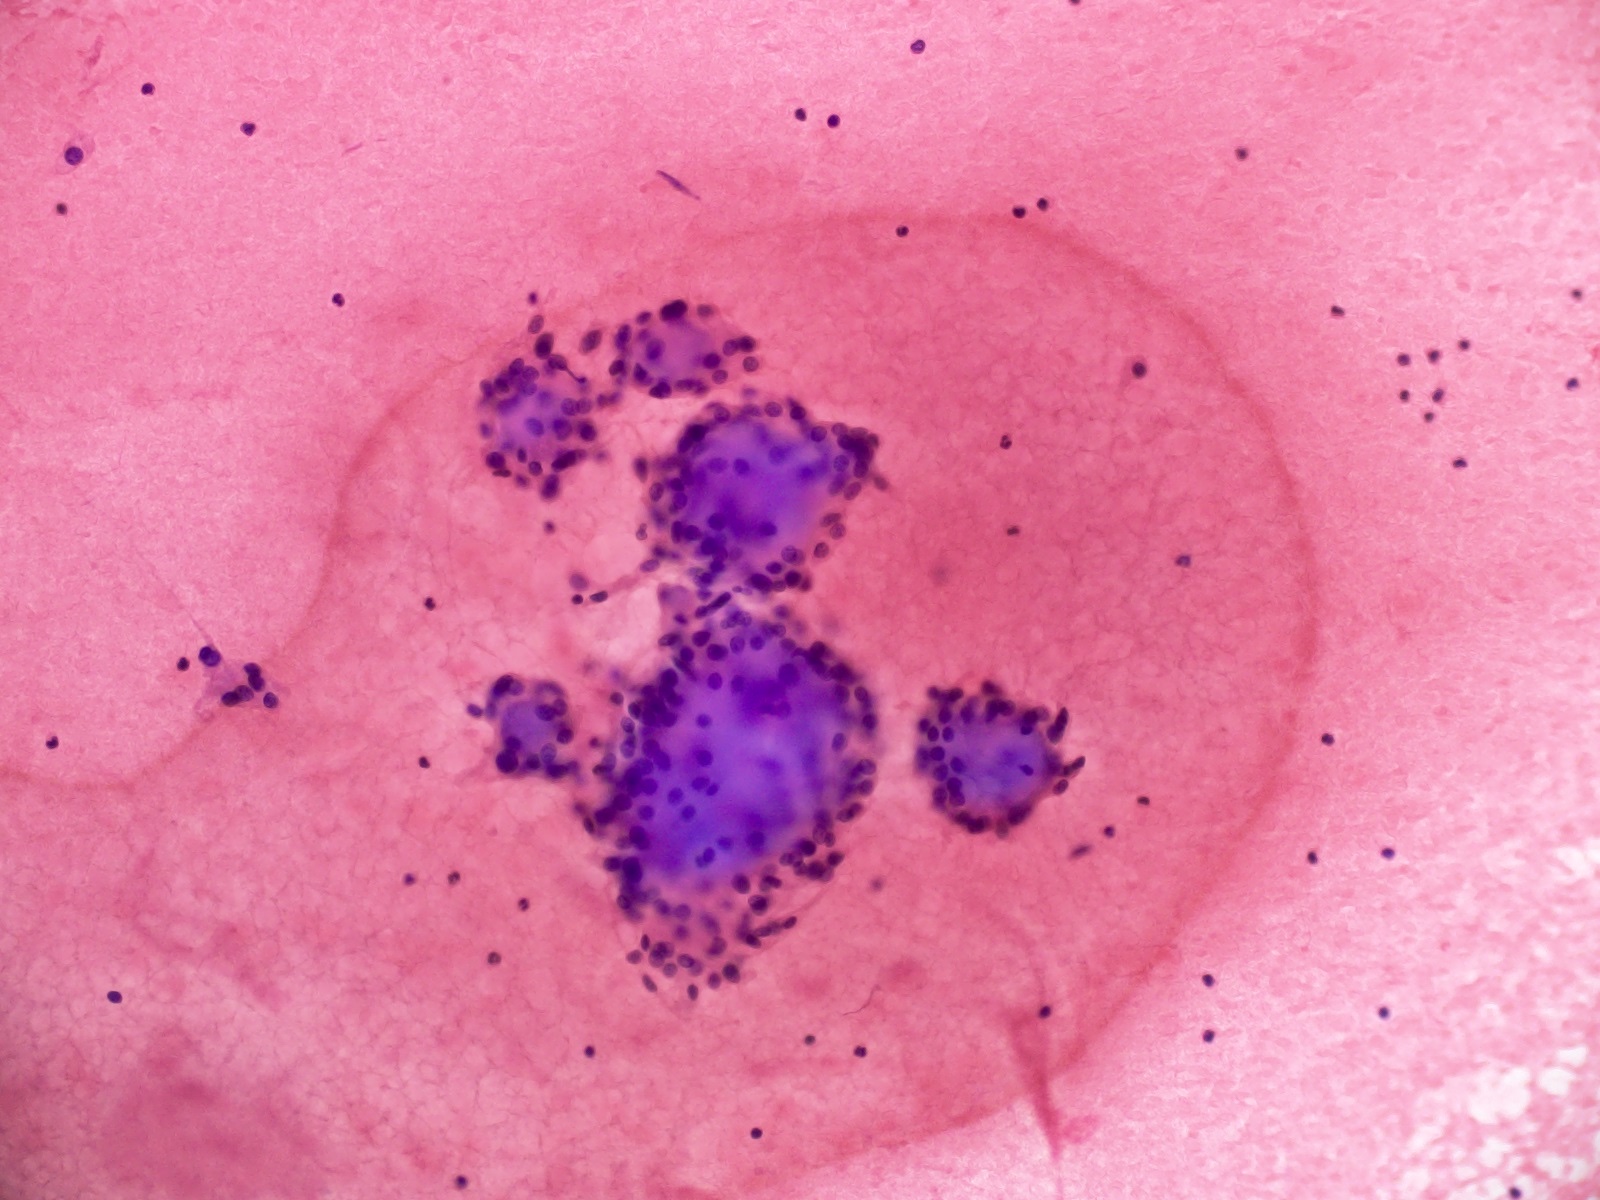

Frozen section description

- Intraoperative squash / smear preparation and frozen section reveals epithelioid to spindled tumor cells arranged around microcysts and forming papillary structures with perivascular myxoid change; these features are diagnostic in the appropriate clinical setting

Cytology description

- Cytology usually recapitulates the histologic findings; myxoid matrix and cells show nuclear uniformity and process formation

- Epithelioid to spindle cells

- Arrangement of tumor cells around blood vessels forms papillary structures with perivascular myxoid change

- Tumor cells are arranged around myxoid microcysts

Cytology images